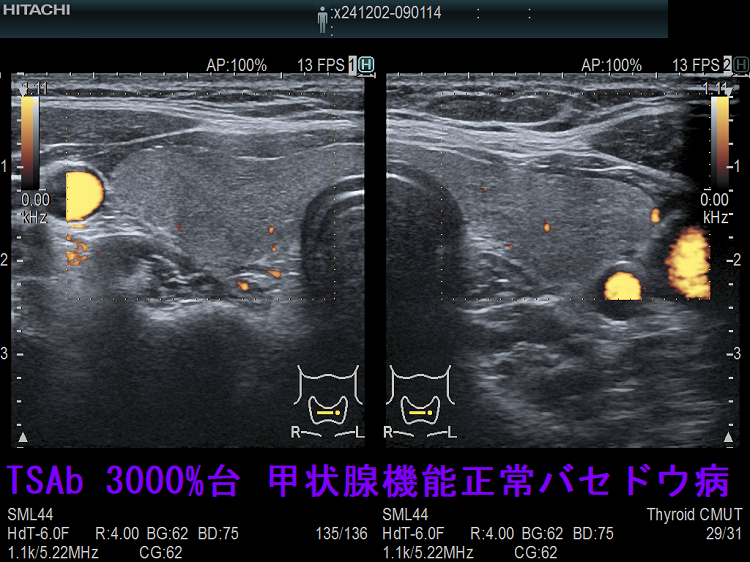

TSAb(TSHレセプター抗体[刺激型]; 甲状腺刺激抗体) 3000%台(正常値<110%)なのに甲状腺機能正常のケースがありました。おそらく、TSBAb(TSHレセプター抗体[阻害型]、甲状腺刺激阻害抗体)とTSAb(甲状腺刺激抗体) が拮抗していると考えられますが、TSBAb(甲状腺刺激阻害抗体)は保険適応外のため測定できませんでした。本当、何とかして欲しいものです。

TSAb(甲状腺刺激抗体) 3000%台 甲状腺機能正常バセドウ病 ドプラーモード